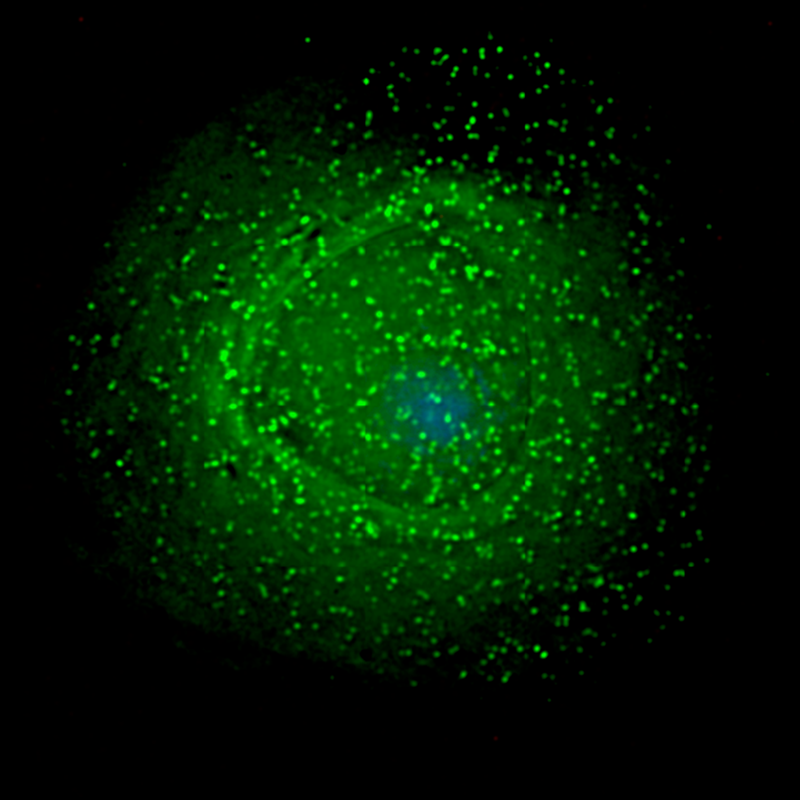

Sangue das lhamas contém anticorpos que neutralizam vírus da Aids